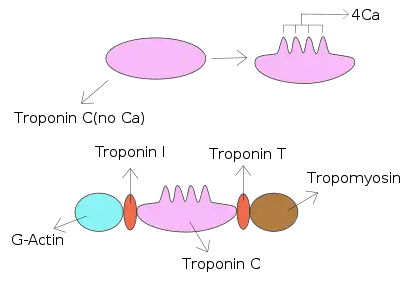

Troponin I is a cardiac and skeletal muscle protein family. It is a part of the troponin protein complex, where it binds to actin in thin myofilaments to hold the actin-tropomyosin complex in place. Troponin I prevents myosin from binding to actin in relaxed muscle. When calcium binds to the troponin C, it causes conformational changes which lead to dislocation of troponin I. Afterwards, tropomyosin leaves the binding site for myosin on actin leading to contraction of muscle. The letter I is given due to its inhibitory character. It is a useful marker in the laboratory diagnosis of heart attack.[2] It occurs in different plasma concentration but the same circumstances as troponin T - either test can be performed for confirmation of cardiac muscle damage and laboratories usually offer one test or the other.[3]